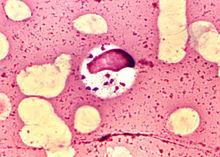

杜氏利什曼原蟲利什曼原蟲Leishmania屬動質體目Kinetoplastida(具1~2根鞭毛,所有的成員都有一動質體,常與根絲體相連,其中含有DNA,位於大的延伸的線粒體內,身體一側有波動膜)。生活史有前鞭毛體(promastigote)和無鞭毛體(amastigote)兩個時期。前者寄生於節肢動物(白蛉)的消化道內,後者寄生於哺乳動物或爬行動物的細胞內,通過白蛉傳播。對人和哺乳動物致病的利什曼原蟲有:引起人體內臟利什曼病的為杜氏利什曼原蟲Leishmania donovani,引起皮膚利什曼病的為熱帶利什曼原蟲Leishmania tropica和墨西哥利什曼原蟲Leishmania mexicana,引起黏膜皮膚利什曼病的為巴西利什曼原蟲Leishmania araziliensis等。我國的黑熱病是由杜氏利什曼原蟲引起的。杜氏利什曼原蟲的無鞭毛體主要寄生在肝、脾、骨髓、淋巴結等器官的巨噬細胞內,常引起全身症狀,如發熱、肝脾腫大、貧血、鼻衄等。在印度,患者皮膚上常有暗的色素沉著,並有發熱,故又稱Kala-azar,即黑熱的意思。因其致病力較強很少能夠自愈,如不治療常因並發病而死亡。解放前,全國黑熱病患者較多。主要流行於長江以北廣大地區,為我國五大寄生蟲病之一。解放後在黨的領導下,在各流行區建立專門的防治機構,發動民眾從治病、消滅病犬和白嶺子三方面進行防治。現已在全國範圍內基本上控制了黑熱病的流行。